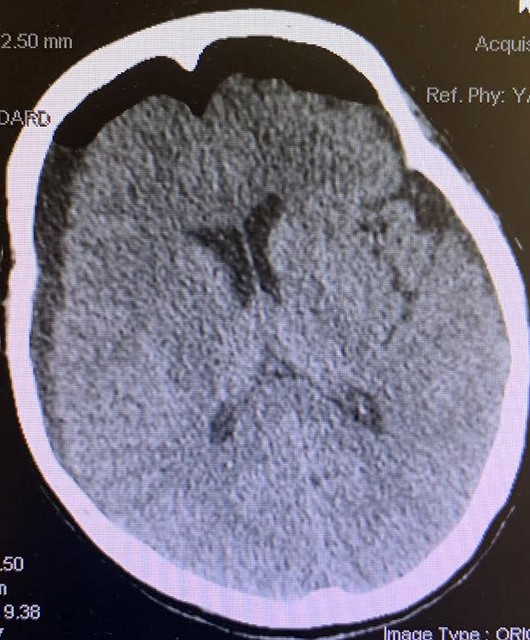

Of note, platelet count started trending down post operative. Patient was on Keppra for seizure prophylactic and due to concern for thrombocytopenia it was switched to Dilantin. On post op date four, patient had a transient episode of urinary incontinence and was aphasic, not answering questions, and staring. A code stroke was activated by nursing staff. STAT CTH showed residual fluid collection measuring 1.2 cm on the right and 0.7 cm on the left, no significant midline shift (Figure 3). The patient returned to baseline neurological status 50 minutes afterward, with no seizure detected on Electroencephalogram (EEG) and continued to improve throughout the remainder of the hospital stay. Discharged occurred on postoperative day 6 with recommendation for follow up with neurology for seizure management and hematology for ongoing evaluation of thrombocytopenia.

Figure 3. CTH axial showed residual fluid collection measuring 1.2 cm on the right and 0.7 cm on the left, no significant midline shift